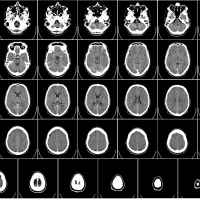

O diagnóstico é feito após avaliação médica com realização do exame físico geral e neurológico, com identificação dos sintomas, seguida da avaliação dos exames complementares, normalmente tomografia computadorizada e ressonância magnética com contraste, que evidenciam detalhadamente a localização e podem orientar o médico em relação ao tipo de tumor.